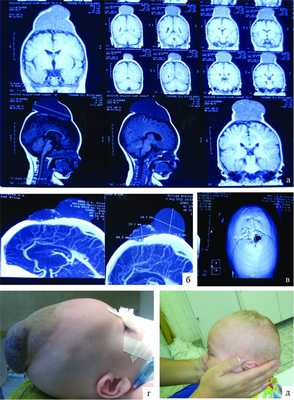

Больной М., 7 лет, поступил в РНХИ им. проф. А.Л. Поленова в отделение нейрохирургии детского возраста в 2012 г. Из анамнеза известно, что в возрасте 2 лет родители отметили наличие мягкотканого образования в правой заушной области. На транскраниальной допплерографии была заподозрена артериовенозная мальформация правой заушной области. При проведении магнитно-резонансной томографии (МРТ) головного мозга заподозрена дуральная венозная мальформация. Жалобы на момент поступления: наличие мягкотканого образования в правой затылочной области. В неврологическом статусе отмечалась легкая координаторная дисфункция. Локально - справа на 3 см выше сосцевидного отростка объемное образование 4,0×4,0 см, мягкоэластичное, при придавливании к костям черепа незначительно уменьшает свой объем. Кожа над образованием не изменена, легко смещаема (рис. 1, д).

Рисунок 1. Наблюдение 1 (больной М.). а - спиральная КТ-ангиография; б - спиральная КТ с 3D костной реконструкцией; в - селективная церебральная ангиография; г - интраоперационные фотографии (этапы операции); д, е - внешний вид больного до и после операции. При проведении спиральной компьютерной томографии (СКТ) с ангиографией с 3D-реконструкцией костей свода и основания черепа определяются гипертрофированные с наличием крупных лакун вены затылочной области справа, которые через дефект в лямбдовидном шве размером 12×9,4 мм дренируются в правую половину поперечного синуса через атипичную эмиссарную вену (см. рис. 1, б). При селективной церебральной ангиографии в артериальную фазу (см. рис. 1, в) данных о наличии артериовенозной мальформации головного мозга не выявлено. Определяется атипичная вена, отходящая от правой половины поперечного синуса, дренирующаяся в экстракраниальную венозную лакуну в правой затылочной области. Больному было проведено оперативное вмешательство, которое заключалось в разобщении правой половины поперечного синуса и экстракраниальных варикозно-расширенных вен и венозных лакун. Интраоперационно отмечалось их спадание (см. рис. 1, г). Трофических изменений кожного лоскута не выявлялось. Больной был выписан под наблюдение невролога (см. рис. 1, е).

Наблюдение 2

Больной Д. поступил в отделение нейрохирургии детского возраста ФГУ РНХИ в 2012 г. с жалобами на наличие патологического образования в области большого родничка, возвышающегося над кожными покровами, синюшного цвета. Анамнез болезни: с рождения в области большого родничка выявлено патологическое образование с синюшным оттенком, венозной сетью. Сразу после рождения отмечалось кровотечение из образования, которое на фоне проводимых мероприятий было остановлено. Увеличение образования, со слов матери, с 2-месячного возраста. В горизонтальном положении ребенка, а также при плаче объемное образование увеличивалось в размере. Местно: в проекции большого родничка объемное образование, синюшного цвета, размером 5×7×4 см (рис. 2, г).

Рисунок 2. Наблюдение 2 (больной Д.). а - спиральная КТ-ангиография; б - спиральная КТ с 3D костной реконструкцией; в - МРТ; г, д - внешний вид больного до и после операции.

При МРТ головного мозга в мягких тканях головы (см. рис. 2, а) выявляется образование, состоящее из двух частей - 30×48 и 40×17 мм. На спиральных компьютерных ангиограммах (см. рис. 2, б) определяется экстракраниальное образование в задних отделах лобной области и медиальных отделах обеих теменных областей, состоящее из двух частей размером 30×48 и 40×17 мм, вызывающих атрофию от давления обеих теменных костей (костный дефект чешуи лобной кости (см. рис. 2, в) в области большого родничка размером 128×25 мм), дренирующееся из передней камеры в среднюю треть верхнего сагиттального синуса; приводящих артериальных сосудов не выявлено. Больному было проведено двухэтапное микрохирургическое вмешательство. В послеоперационном периоде признаков венозной гипертензии не отмечалось, очаговая симптоматика не выявлена, косметический дефект отсутствует (см. рис. 2, д).